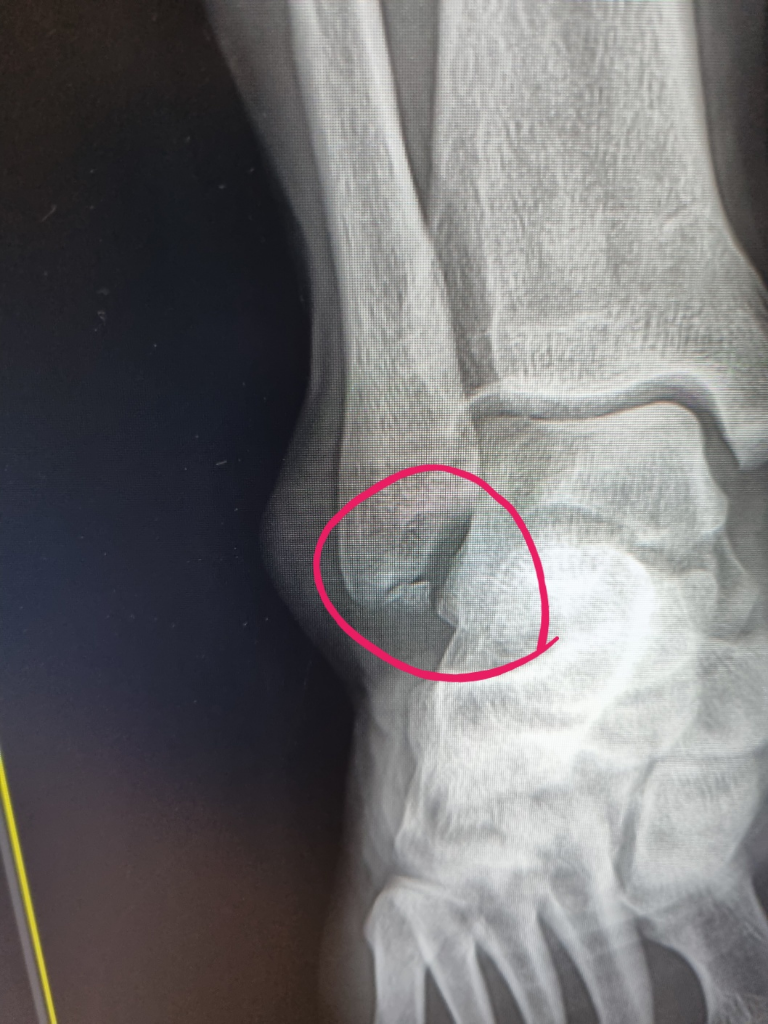

복숭아 뼈 밑 쪽이 골절이라고 하네요....

• 1번 째 사진

• 골절이 발생하였다고 무조건 수술적 치료를 하는 것은 아닙니다. 올리신 엑스레이 사진 소견만으로 수술이 필요하다 또는 필요하지 않다 판단할 수 없습니다. 사진으 소견만 보았을 때에 골절의 정도가 심하지 않긴 하지만 인대 손상이 동반이 되었거나 CT 또는 MRI 촬영을 하였을 때 뼈가 어긋난 정도가 심하다면 수술적 치료의 적응증이 될 수 있습니다. 그렇기 때문에 결국엔 정형외과 진료를 보고 더 정밀하게 상태를 파악하여야 판단이 가능할 것입니다.

골절은 맞는 것 같네요. 수술 여부는 급한것은 아니라서 정형외과에서 상의 후에 결정하는 것이 좋겧습니다. 깁스만 하고 4~6주 지켜보는 것도 가능할 것 같습니다.

수술할 가능성이 높아보이진 않습니다.

하지만 한 면의 x-ray 로는 정확한 판단이 불가능하고, 여러면의 x-ray 혹은 CT, 신체진찰을 종합적으로 판단하여 수술여부를 결정하기 때문에 정형외과 방문하시어 의견을 들어보시는 것이 좋겠습니다.

비골 골절에 대한 수술 여부는 엑스레이와 환자 나이, 활동정도 등을 고려해서 결정합니다. 추가 엑스레이나 CT영상 등으로 정확하게 판단하게 되며 비골골절이 발목 부위에서 발생하고 불안정한 골절이라면 수술적 치료가 필요합니다.